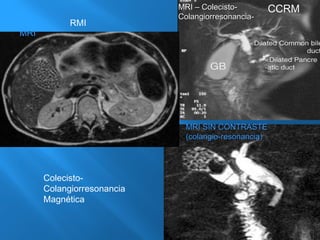

3.- RMI (Colangiorresonancia)

MMRRII –– CCoolleecciissttoo--

CCoollaannggiioorrrreessoonnaanncciiaa--

MMRRII SSIINN CCOONNTTRRAASSTTEE

((ccoollaannggiioo--rreessoonnaanncciiaa))

MRI

RMI

Colecisto-

Colangiorresonancia

Magnética

CCRM